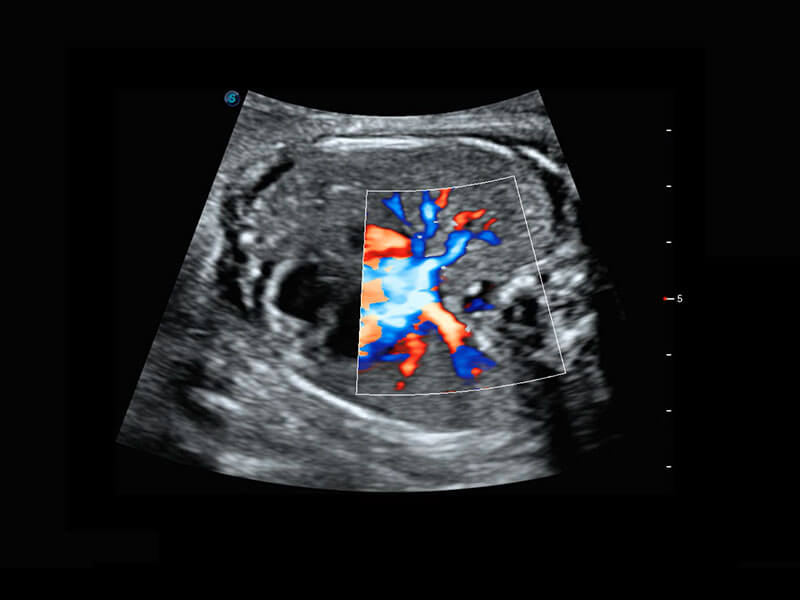

• 胎儿体循环

胎心筛查

P60搭载一系列胎儿心脏成像技术,实现精细的胎儿心脏评估。